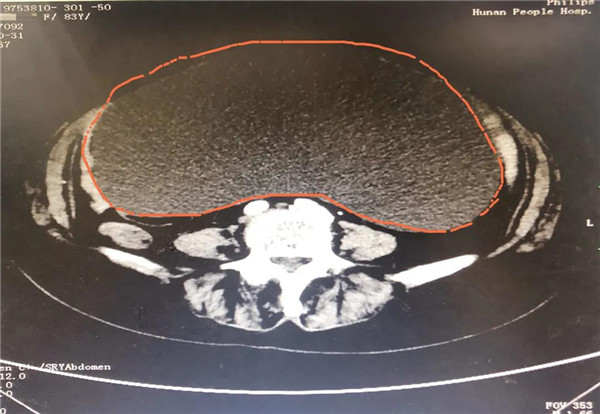

CT显示,巨大的肿瘤几乎占据老人整个盆腔和腹腔。

2021年10月29日,彭娭毑住进湖南省人民医院妇科病房。完善相关检查发现,巨大的肿瘤几乎占据她整个盆腔和腹腔,并且压迫肠道和膀胱,这也是老人尿频的原因。与此同时,术前血液检查发现了异常——全系细胞减少;进一步骨髓穿刺结果为:可疑B细胞淋巴瘤骨髓浸润。